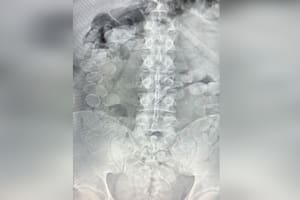

Al dar el parte médico sobre su estado, las autoridades indicaron que la víctima sufrió un trauma cerrado de tórax y craneoencefálico, múltiples fracturas costales y en la clavícula izquierdas con hemotórax izquierdo laminar, y una contusión hemorrágica temporal derecha con hemorragia subaracnoidea traumática.